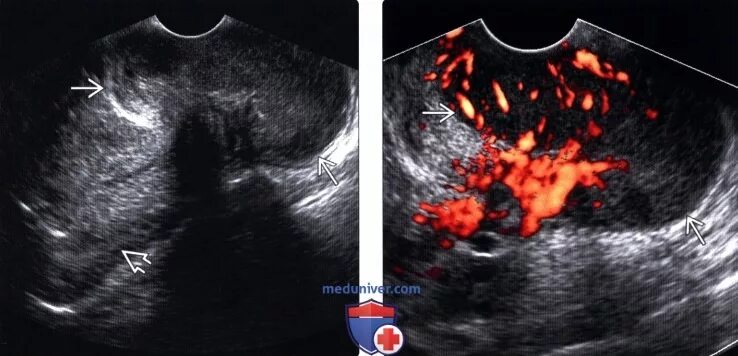

Гематометра симптомы